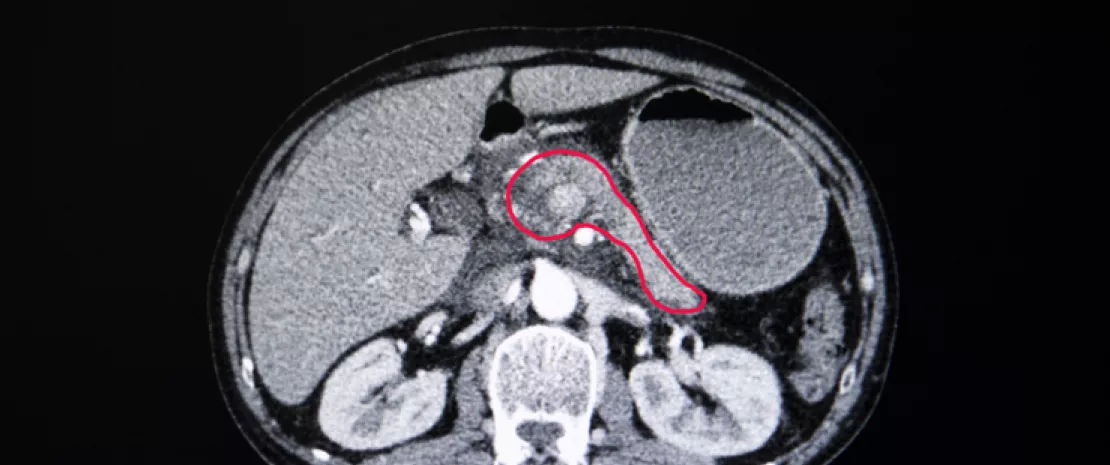

ABD'de en yaygın üçüncü kanser kaynaklı ölüm nedeni olan ve 5 yılda sağkalım oranı %9 olan PDAC çok korkulan bir kanser türüdür. Daha önce yapılan çalışmalar PDAC hastalarının tümör mikrobiyotasının, duodenumdan gelmiş olduğu düşünülen normalde üst gastrointestinal sistemde mevcut bakteriler içerdiğini göstermiştir. Durum buysa duodenum sıvısı PDAC hastalarının veya PDAC oluşma riski olan hastaların mikrobiyom profillerini belirlemek için temsili bir biyo-örnek olabilir. Bundan dolayı 134 normal pankreaslı kişiden(kontrol), 98 pankreas kisti olan hastadan ve 74 PDAC hastasından duodenal endoskopi ile toplanan duodenum sıvısının bakteri ve mantar profillerini karşılaştıran bu tek merkezli vaka-kontrol çalışması yapıldı.